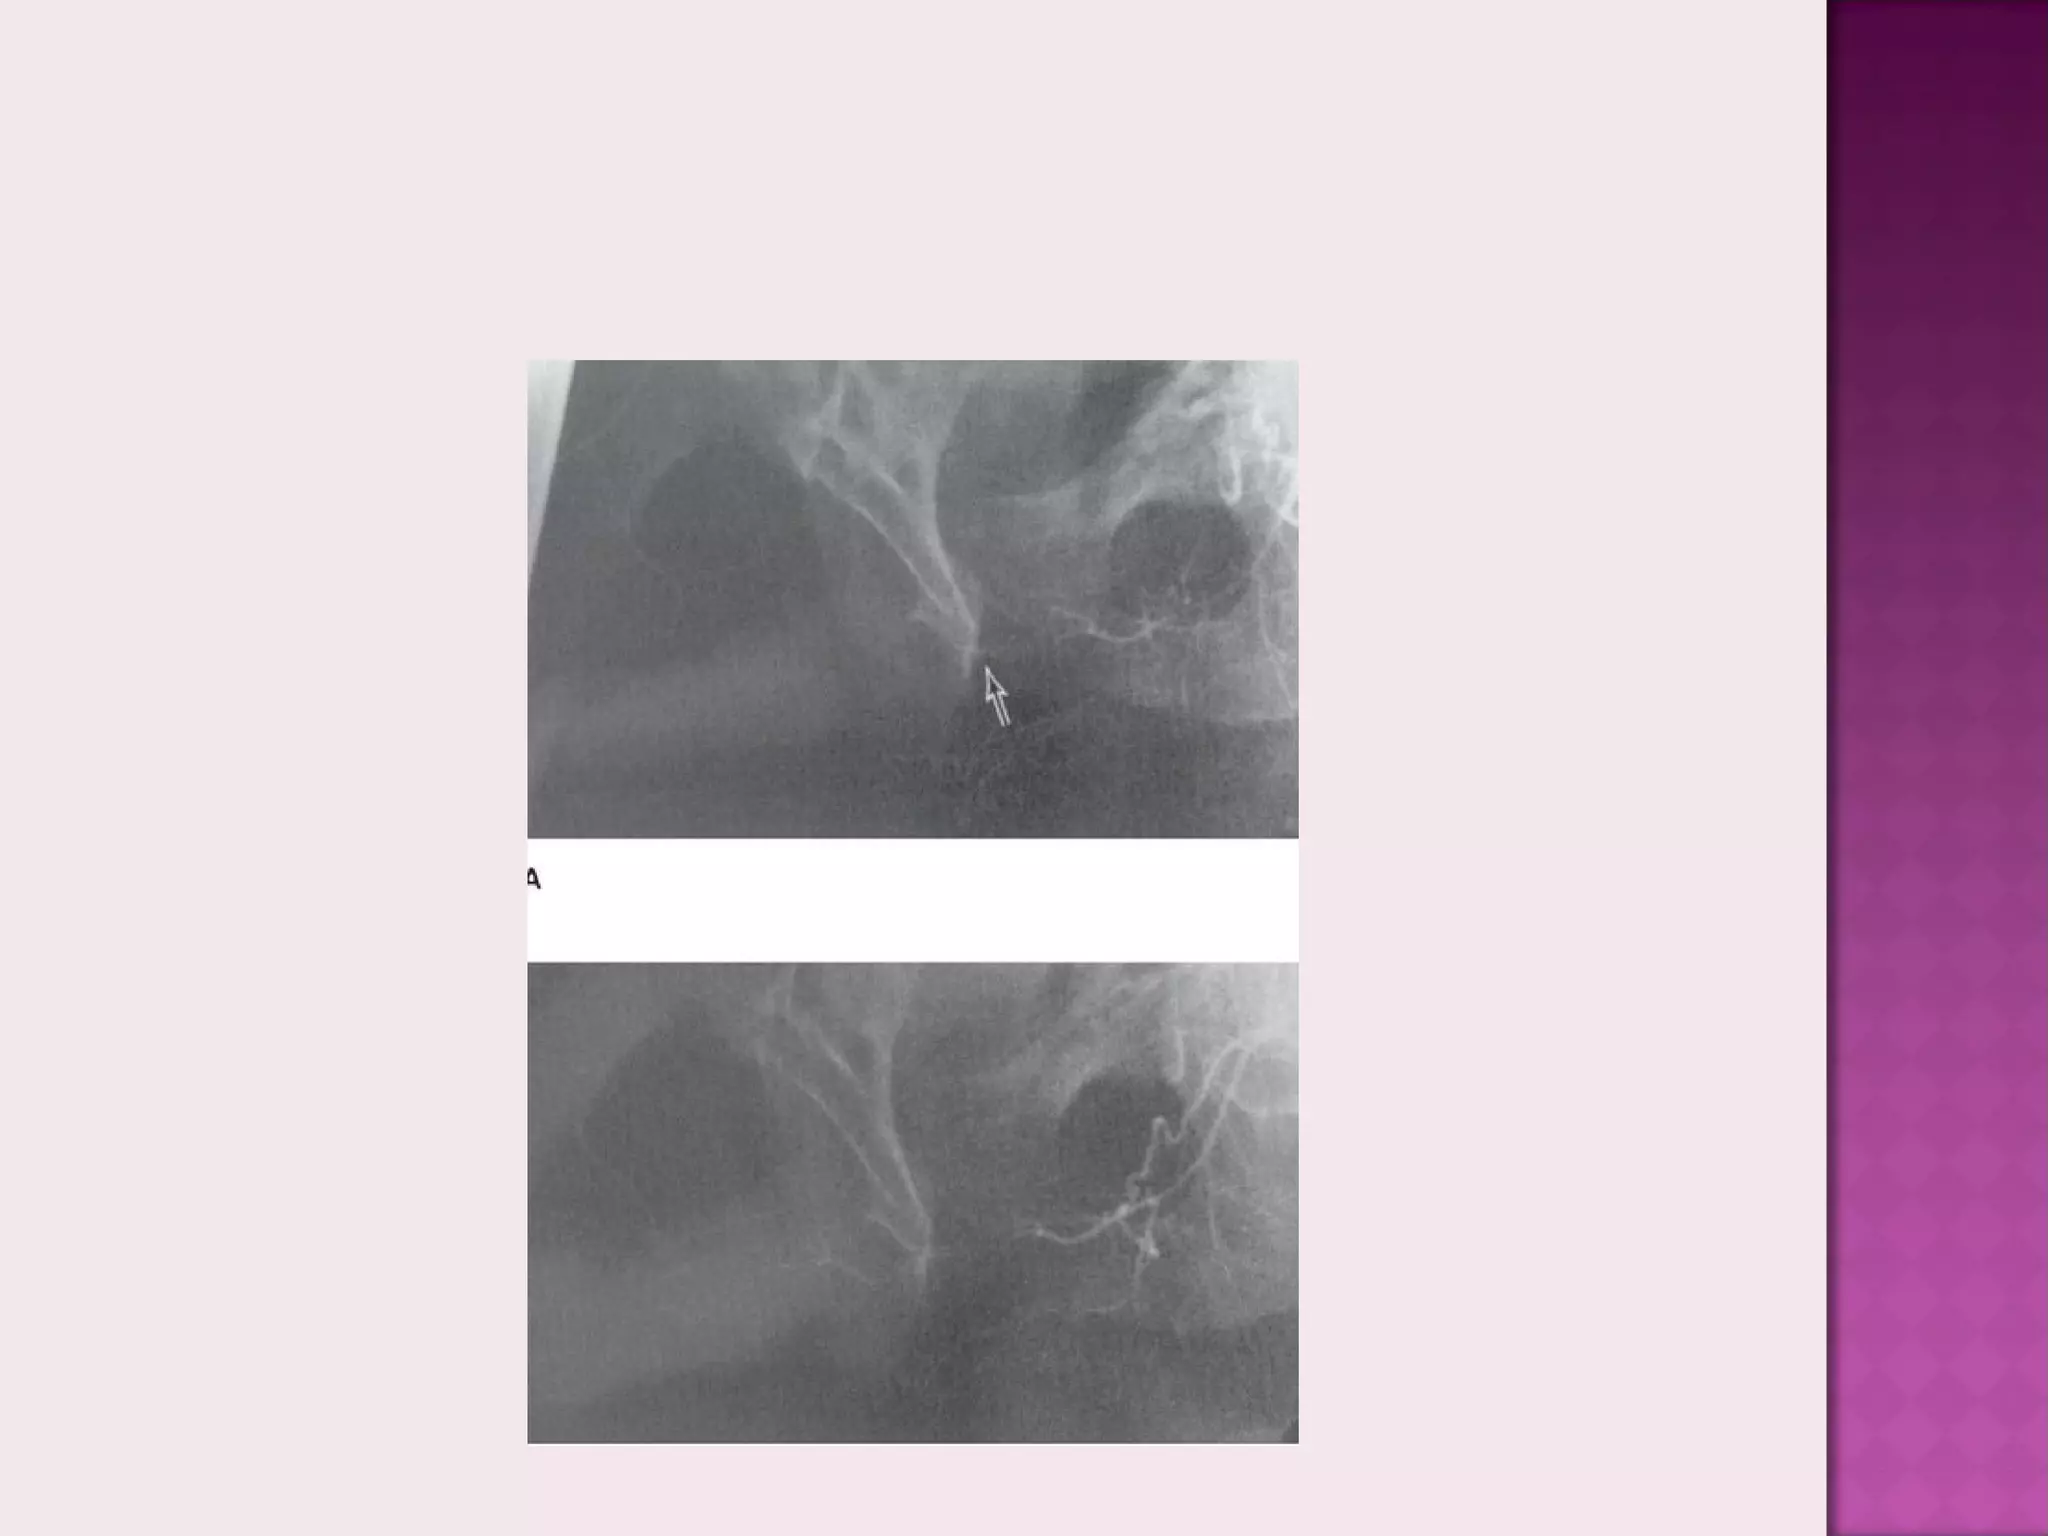

 Name this

investigation ?

 Dynamic infusion

cavernosgraphy

 What is the

finding shown?

 Venous leakage along

pelvic veins